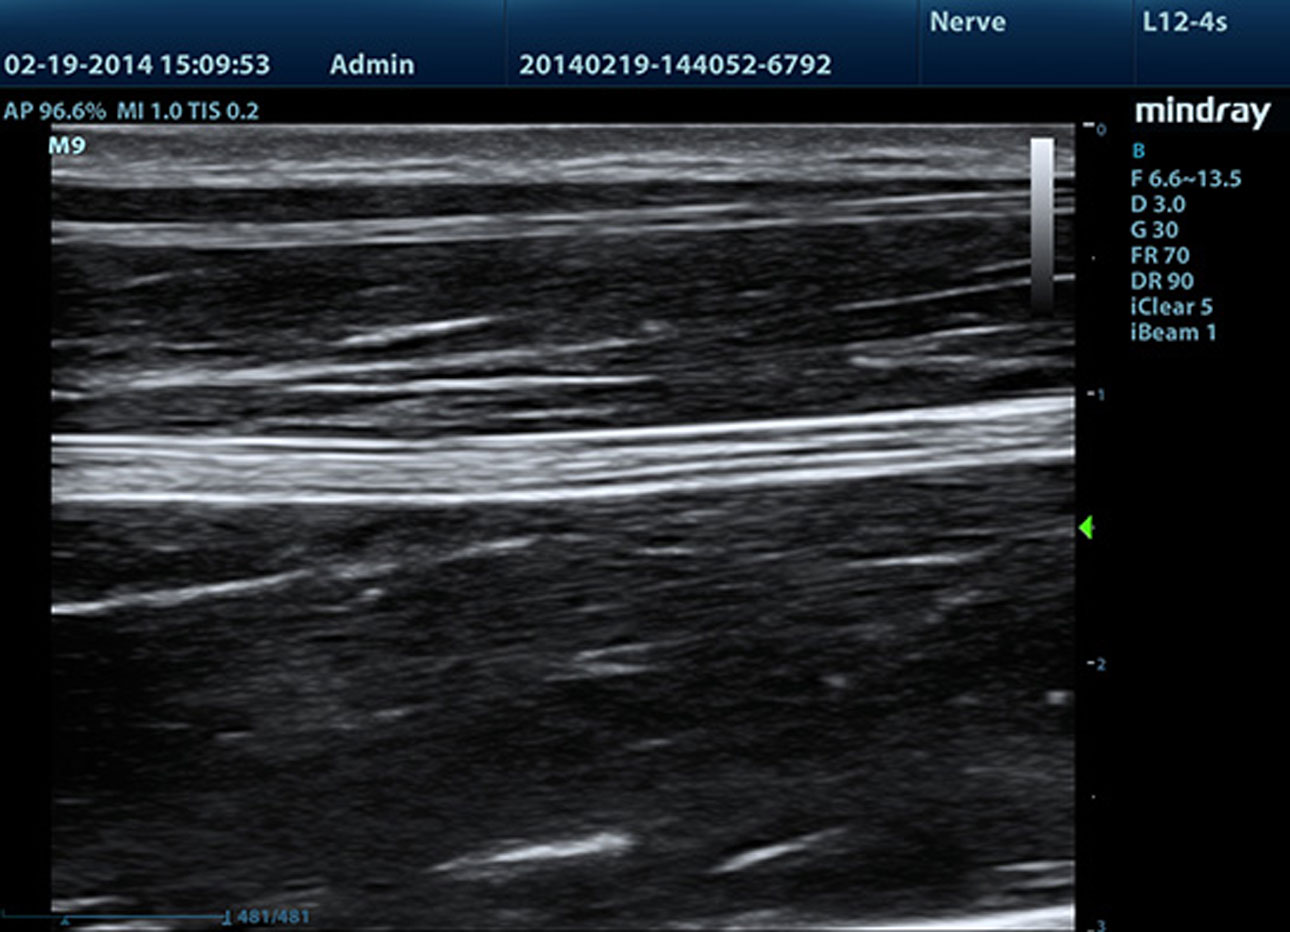

B-Steer/ iNeedleTM

Su herramienta para una biopsia m├Īs profunda: permite ajustar la l├Łnea de escaneo para obtener una mejor visibilidad de la aguja, los nervios y los vasos peque?os.